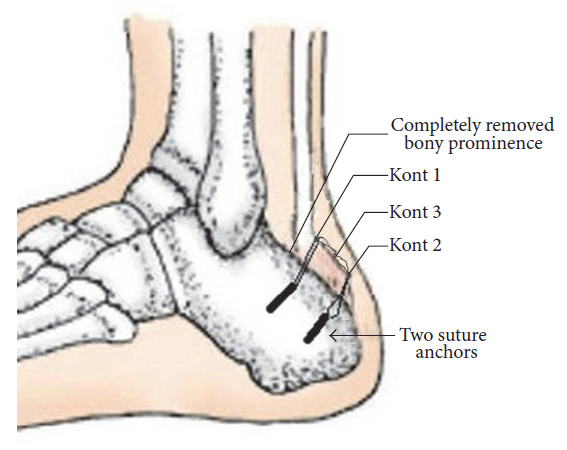

止点变性和钙化严重导致彻底清理后跟腱止点缺损超过50%时需要行跟腱止点重建。

50%-70%的跟腱止点切断,一枚锚钉固定:

跟腱完全从止点切开,用两枚单排锚钉固定:

双排锚钉固定相对于传统单排锚钉固定临床效果更好,满意度更高: